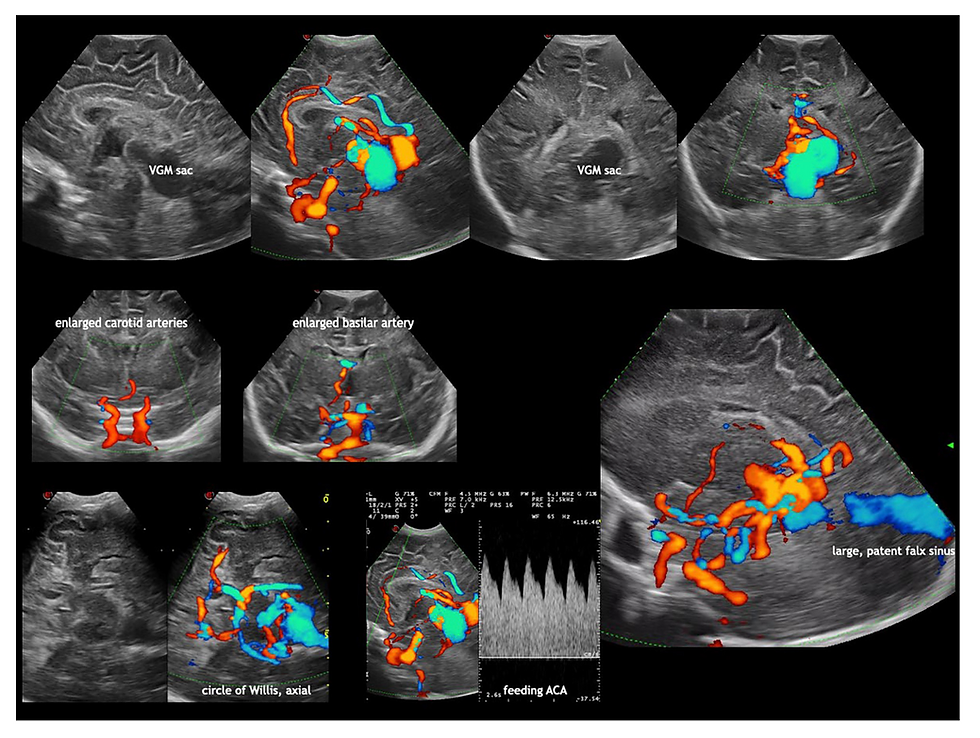

El paso más importante para la confirmación del diagnóstico es la evaluación de la tumoración con Doppler que muestra un flujo caótico. Las características de las arterias alimentadoras serán muy importantes para el pronóstico puesto que su tamaño y número determinarán el grado de shunting y la obliteración completa de la totalidad de estos vasos mediante embolización será la única alternativa de tratamiento eficaz. La magnitud del compromiso de los vasos puede evaluarse con Doppler, tal como lo muestra Horsch en su revisión reciente (Dev Med & Child Neurol, 2024):

La flujometría Doppler mostró alto flujo sistólico y bajo flujo diastólico (IR bajo) en la arteria pericallosa confirmando su naturaleza alimentadora de esta arteria. Se espera un patrón inverso (con alto IR) en casos de vasos no comprometidos con la fístula, como las arterias piales y corticales, lo cual producirá isquemia de sus territorios con progresiva destrucción del parénquima cerebral.